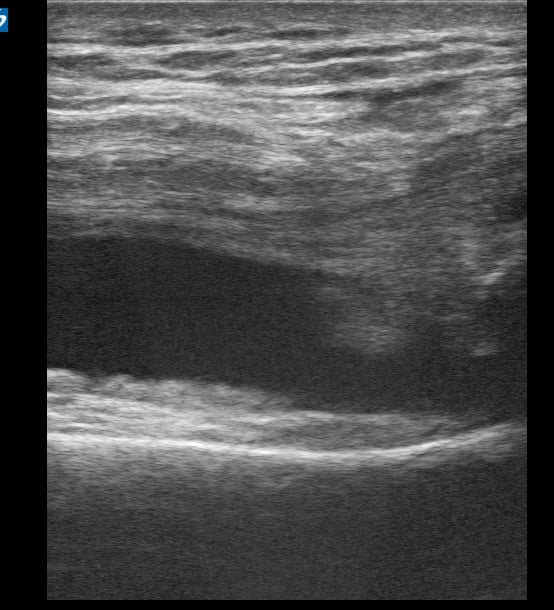

Knee effusion, in musculoskeletal (MSK) ultrasound, refers to the abnormal accumulation of fluid within the knee joint capsule. This common medical finding can indicate various pathologies, including trauma, inflammation (like arthritis), or infection. Ultrasound is a highly effective tool for detecting and quantifying knee effusions, allowing clinicians to assess fluid volume, characterize its nature (e.g., anechoic, complex), and guide aspiration procedures for diagnostic or therapeutic purposes.

Accurate identification of knee effusion via ultrasound is crucial for guiding patient management in sports medicine and orthopedics. Its real-time capabilities and portability make it an indispensable imaging modality for rapid diagnosis and monitoring of joint conditions, aiding in precise medical interventions and optimizing patient outcomes.